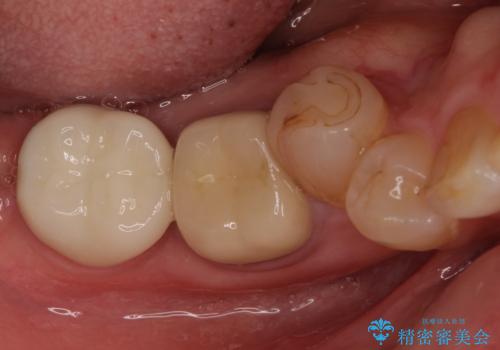

- 抜歯が必要と診断された奥歯の治療を希望して来院された患者様です。

一番奥の歯は歯根の一部を残した状態で、手前の歯とブリッジが装着されていました。

奥歯は歯根周辺の歯槽骨が広範囲に失われており、抜歯が必要と判断されました。

ブリッジの手前側の歯は、根管治療が必要な状態でした。

手前は根管治療後に補綴治療を、奥は骨造成後にインプラント埋入し、手前の歯と同時に補綴治療を行うこととしました。